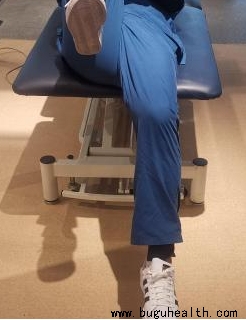

- 布骨医学科普:一个动作看出髋膝周围肌肉问题 布骨康复医疗中心 ,2021-11-16

- 久坐腰痛... 髋关节外侧弹响...膝盖外侧持续的疼痛...骨盆前倾、X或O型腿、外八字脚...这些有可能是髋周围或者腿上的一些肌肉变得紧绷而导致;在我们提出解决这些紧绷的肌肉之前,我们需要知道是谁?它是否真的紧?.....